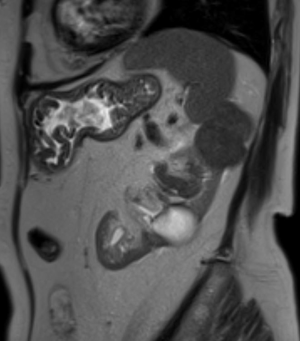

МР-диагностика образований поджелудочной железы